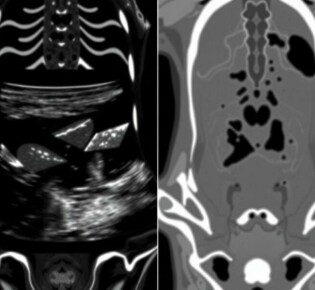

El misterio revelado: Comprendiendo la anatomía del apéndice